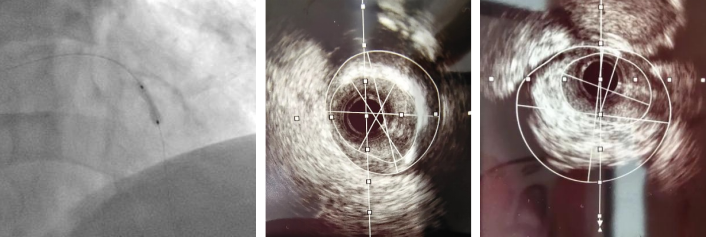

切割扩张后

患者为一名67岁的男性,于一月前因“反复活动后胸痛5年”入院,于右冠脉植入支架一枚。术后患者活动后胸痛较前未见明显缓解。11月9日患者返院,心血管内科二病区根据病人情况,再次为患者行PCI治疗。术中因尝试使用“预扩张球囊”于病变处扩张后效果差,但再次使用“切割球囊”于病变处切割后依旧可见钙化斑块难以充分扩张。通过血管内超声(IVUS)可见左前降最小管腔面积仅1.8mm2,深层大于270°环形钙化斑。